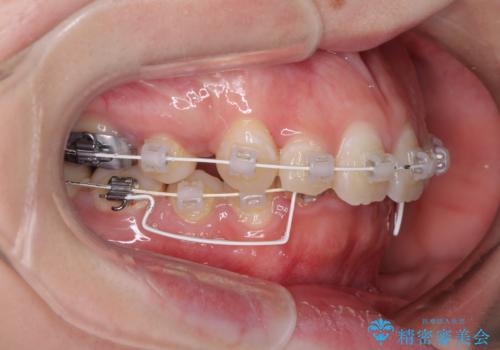

- 審美装置

下顎小臼歯の欠損により過蓋咬合となっていたため、下顎は臼歯を起こすことで咬み合わせを改善し、八重歯は第一小臼歯2本を抜歯し、補助装置を使用して速やかに改善することとしました。

八重歯は3,4か月で速やかに改善されました。